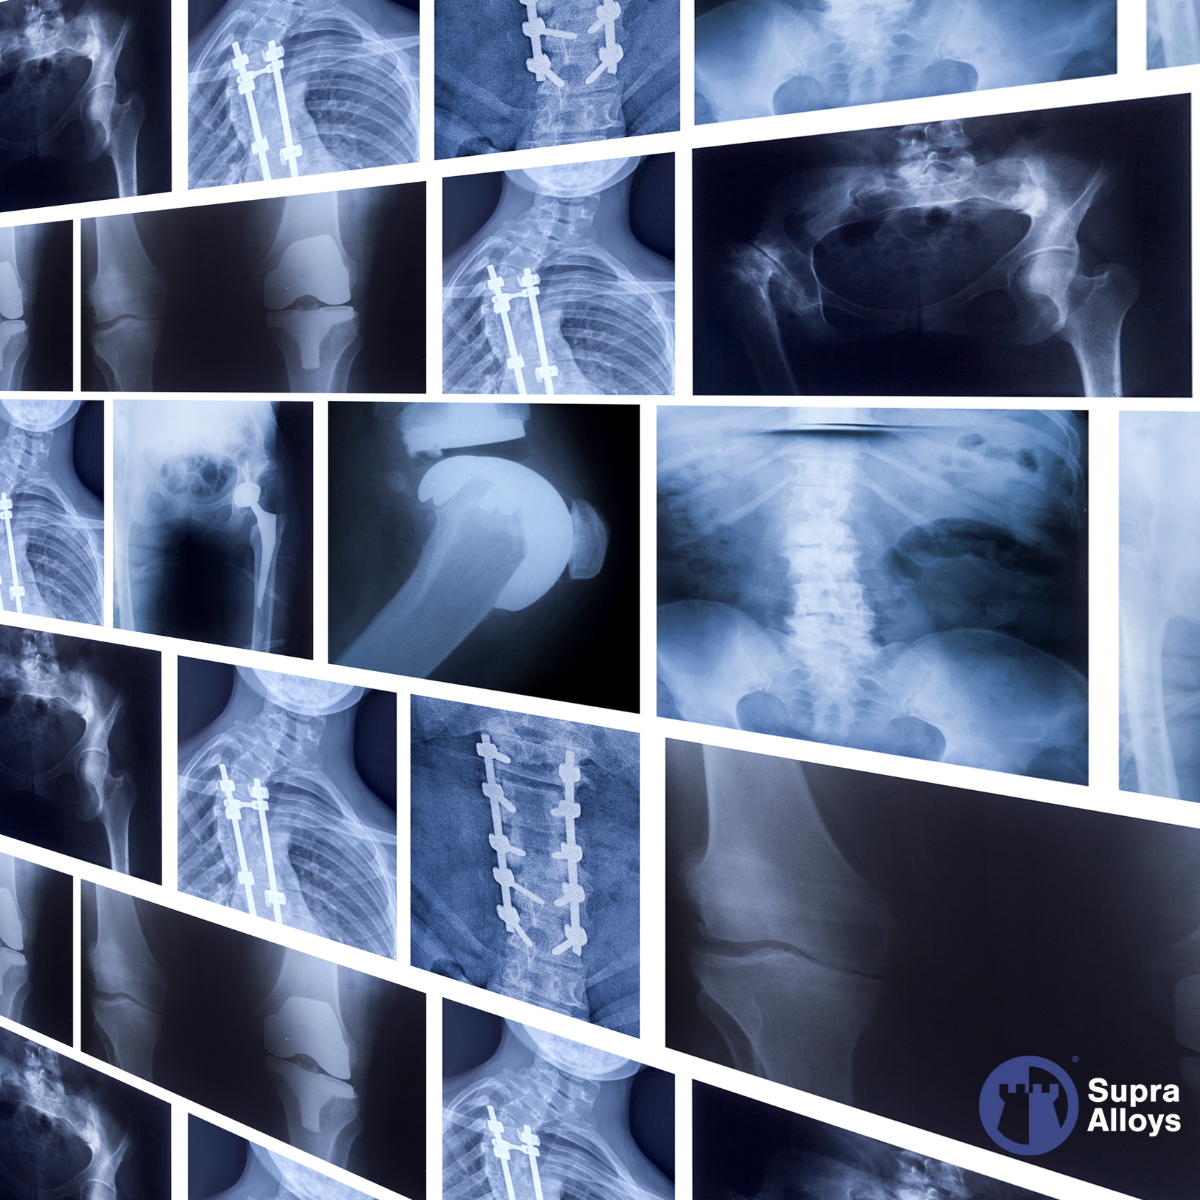

Medical: Advancing Healthcare with Biocompatible Metals

In the medical sector, Supra Alloys supplies titanium rod and wire for surgical instruments, orthopedic implants, and prosthetic devices. Titanium’s biocompatibility and corrosion resistance make it the material of choice for bone and joint replacements, dental implants, and life-saving medical devices. Our ISO 13485:2016 certification for medical devices guarantees that every product meets the highest standards for safety and performance.